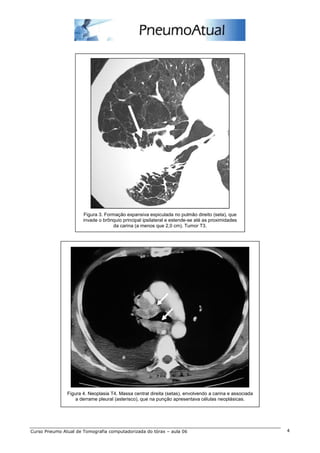

Figura 3. Formação expansiva espiculada no pulmão direito (seta), que

invade o brônquio principal ipsilateral e estende-se até as proximidades

da carina (a menos que 2,0 cm). Tumor T3.

Figura 4. Neoplasia T4. Massa central direita (setas), envolvendo a carina e associada

a derrame pleural (asterisco), que na punção apresentava células neoplásicas.